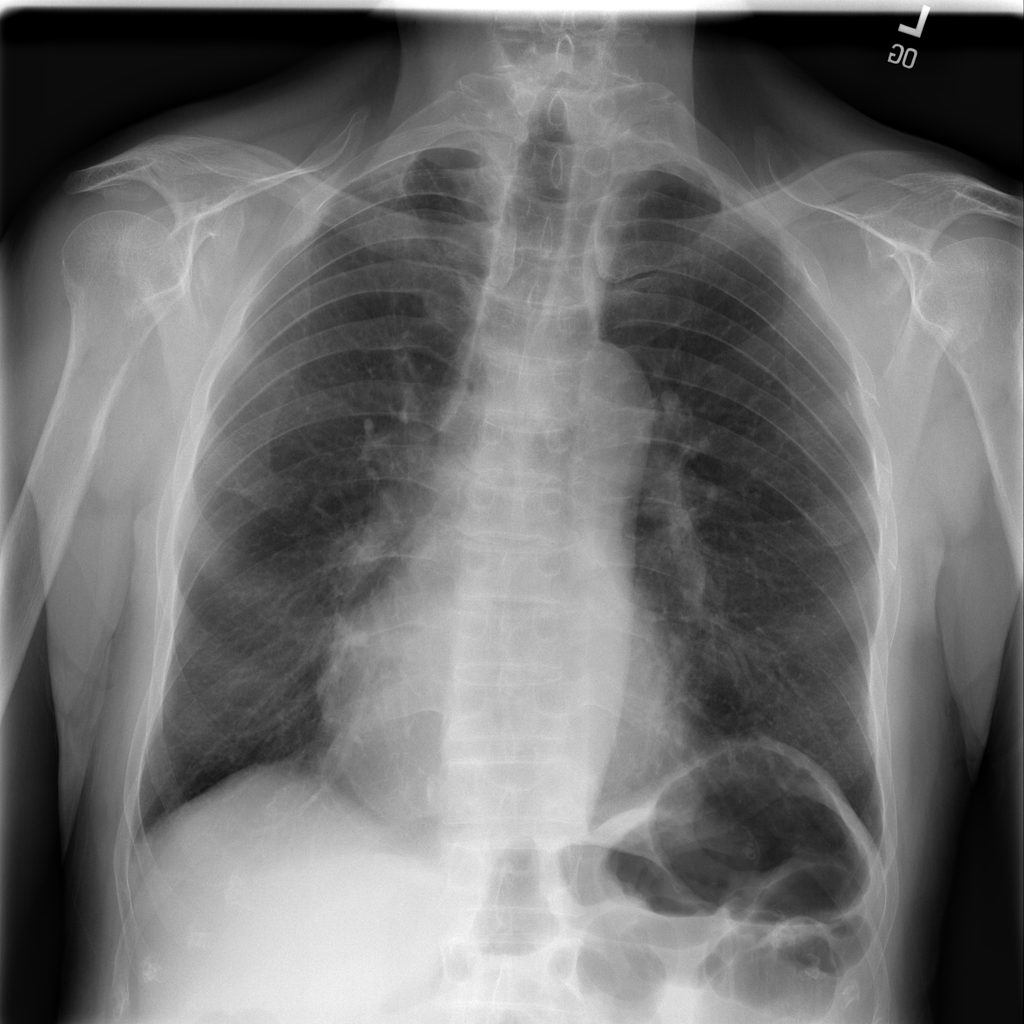

Showing up to 90 reference images for Cardiomegaly.

PAT-F3E7 · IMG-000Cardiomegaly

PAT-F3E7 · IMG-000

PA